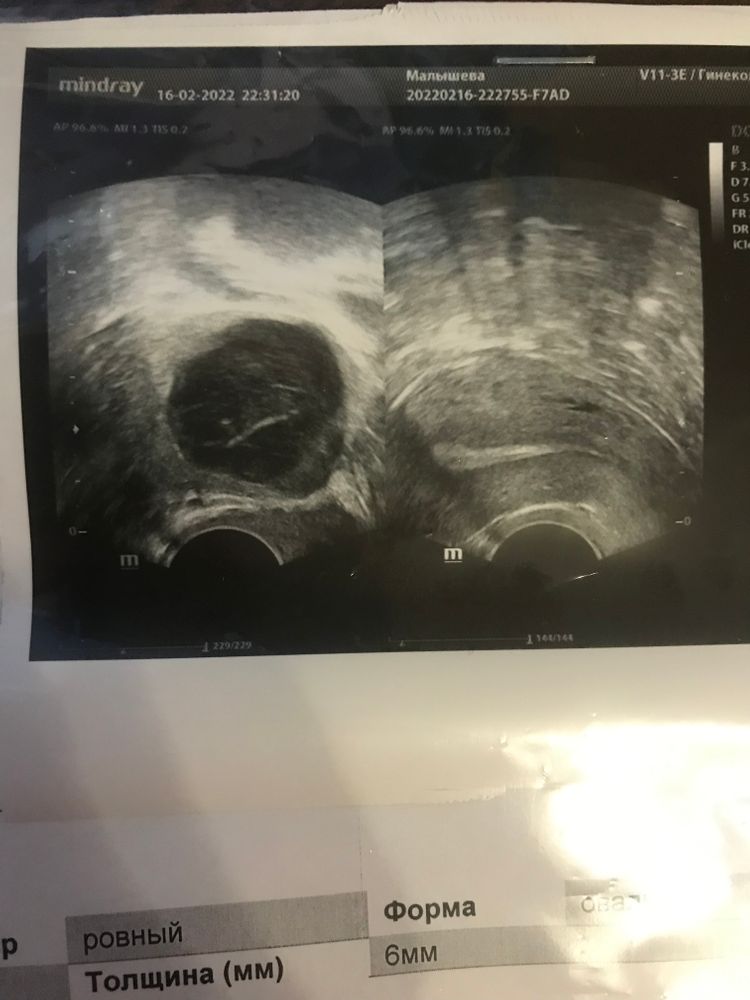

Узи 8 дпо ( 17дц)

эндометрий на 11 дц был 9

стал меньше

жт огромное, а прогик пришёл 7,2 нг/мл